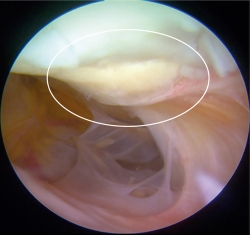

Figura 2. Técnica de implante artroscópico en patela. A: en la parte superior se muestra el implante siendo perforado con aguja hipodérmica para pasar la sutura PDS del lado que contacta con la superficie ósea al lado articular y de nuevo al lado que contacta con la superficie ósea. Abajo se muestra cómo queda el implante una vez pasada la sutura; B: en la parte superior se muestra cómo se introducen los extremos libres de la sutura PDS en el ojal de los alambres pasasuturas, los cuales al traccionar permiten recuperar los extremos de la sutura a través del abordaje anterior. Abajo se muestra una vista artroscópica en la cual la sutura PDS ya se ha recuperado por el abordaje anterior; C: en la parte superior se muestra una vista artroscópica dirigida a través de la cánula de 10 mm en la que se observa cómo el implante desciende al traccionar la sutura PDS. En la parte inferior de muestra el implante situado y cubriendo el sitio de la lesión. La línea blanca delimita el implante.